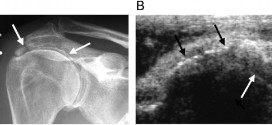

Leer MásCERVICOBRAQUIALGIA

La cervicobraquialgia. Es una radiculitis inflamación de las raíces nerviosas de los nervios espinales, en concreto del plexo braquial que se manifiesta por dolor muy fuerte y continuo en la región posterior y externa del cuello y la nuca. Información: Para más información sobre esta enfermedad o patología, si usted cree que es necesario, preguntar a su médico o especialista, …

Leer MásCERVICOARTROSIS

La cérvicoartrosis. Es la artrosis que afecta a la zona de la columna vertebral cervical y que suele iniciarse a partir de aproximadamente a los 40 años. Ataca con más frecuencia las articulaciones intervertebrales anteriores, donde aparecen formaciones óseas (osteofitos) que pueden llegar a reducir el canal vertebral y ocasionar compresión medular seria. El disco intervertebral también se lesiona (fisuraciones, …